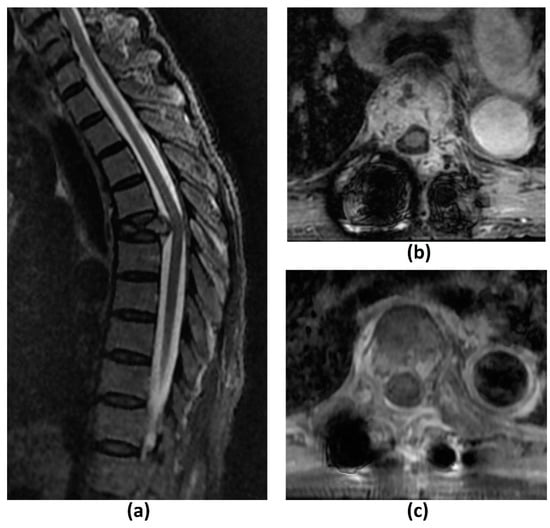

| T2-W | Evaluation of spinal cord and nerve root compression (‘myelogram-like effect’); Detection of cord signal changes (e.g., myelomalacia or oedema) | Suboptimal for evaluation of marrow replacing lesions |

| T1-W | Identification of marrow replacing lesions including metastasis; Useful for comparison with post-contrast sequences to identify true contrast-enhancement | Suboptimal for evaluation of spinal cord and nerve root compression; Peritumoural oedema may also appear hypointense on T1-W sequences, which may limit the accuracy of measurement of the true tumour size |

| T1-W post-contrast FS | Detection of enhancing vertebral metastasis, sites of leptomeningeal and intramedullary disease; Delineation of tumour extent including identification of the epidural component, and presence of foraminal or paraspinal extension; Determination of biopsy site of highest yield (if biopsy required) | Suboptimal for evaluation of spinal cord and nerve root compression |

| STIR | Identification of marrow replacing lesions including metastasis; More accurate measurement of true tumour size from surrounding peritumoural oedema than T1-weighted sequences; Identification of macroscopic fat in lesions | Suboptimal for detection of sclerotic vertebral metastasis without oedema |